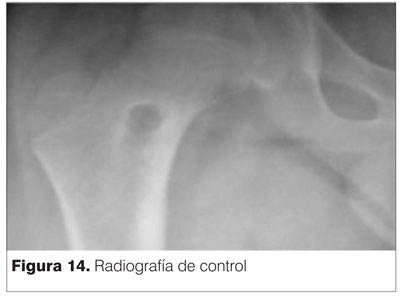

A los 6 meses del postoperatorio el paciente se encuentra totalmente asintomático. Se permite retomar actividad deportiva curricular escolar. En las radiografías de control persiste la imagen secuelar de la punción, pero con trama ósea que evoca el relleno de la cavidad (figura 14).

Clínicamente no presenta dolor y la movilidad activa y pasiva al examen físico es completamente indolora.

Se considera que la resección fue completa con curación de la patología tumoral. Aún continúa con controles clínicos.